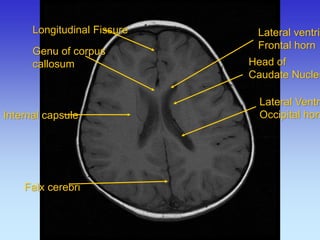

Longitudinal Fissure

Genu of corpus callosum

Internal capsule

Falx cerebri

Lateral ventricle,

Frontal horn

Head of Caudate Nucleus

Occipital horn